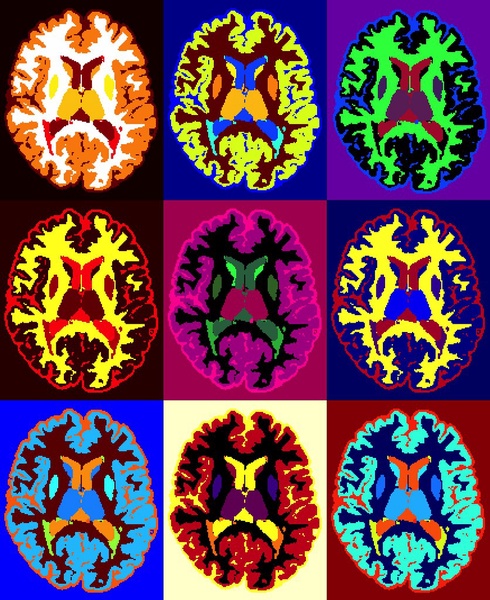

Ciertamente, el hallazgo patológico más característico de la EM es la presencia de múltiples placas de desmielinización. Se observan lesiones progresivas en amplias estructuras cerebrales (sustancia blanca en el SNC, hemisferios cerebrales, cerebelo y tallo cerebral), junto a un importante deterioro de la integridad axonal.

Así, desde etapas tempranas de la enfermedad se producen lesiones (inflamatorias en la sustancia blanca y gris, desmielinización y daño axonal) que provocan que la funcionalidad de la persona se limite progresivamente.